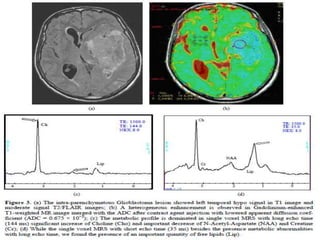

A 52-year-old male with high grade tumor (glioblastoma, WHO grade IV) was

misdiagnosed as low grade tumor due to nonspecific MRS pattern and too small number

of VOIs. A and B, T2 high signal intensity lesion is noted in the right hippocampus and

anterior temporal lobe without definite contrast enhancement (A: T2-weighted image,

B: postcontrast T1-weighted image). C and D, MR spectroscopy of the mass shows slightly

increased choline, interpretating as low grade tumor.